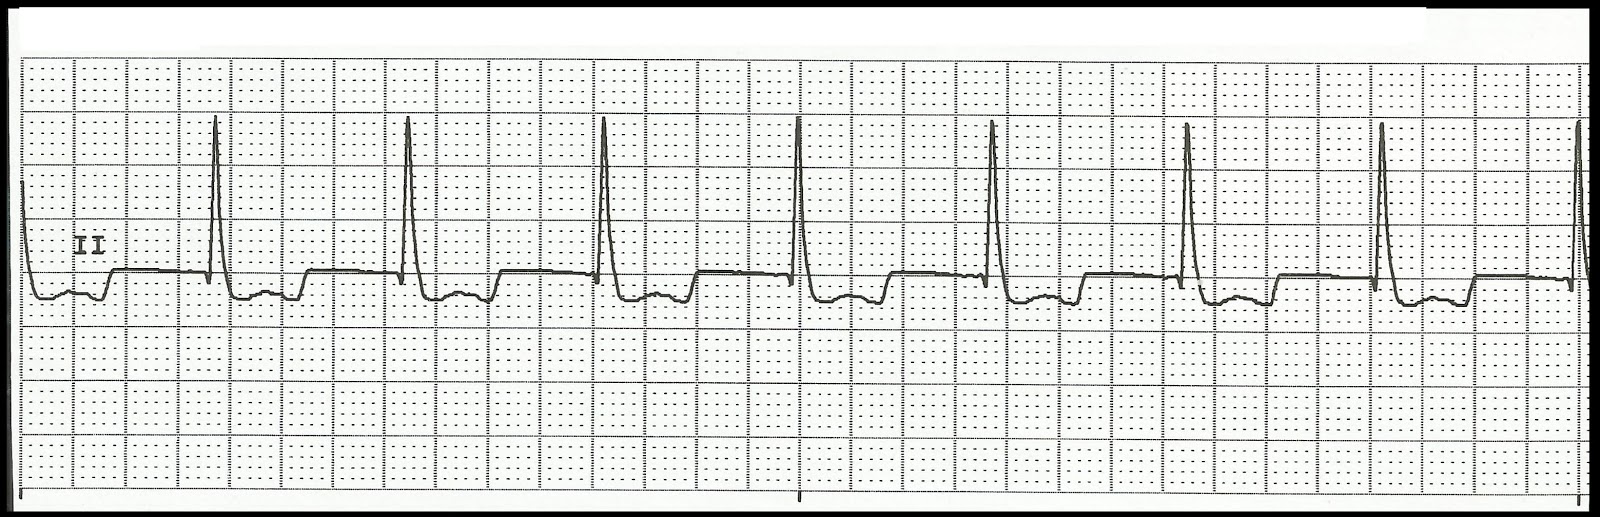

Holter ECG showing an accelerated junctional rhythm (AJR). Download Can Accelerated Junctional Rhythm Be Irregular Junctional tachycardias, which originate in the av junction (including the his bundle), can be regular or. Having an accelerated junctional rhythm occurs when the atrioventricular node in your heart beats too quickly. Accelerated junctional rhythm is when the rhythm of emerged impulses is more than 40 to 60 beats per minute, which is the natural range of the. It happens. Can Accelerated Junctional Rhythm Be Irregular.